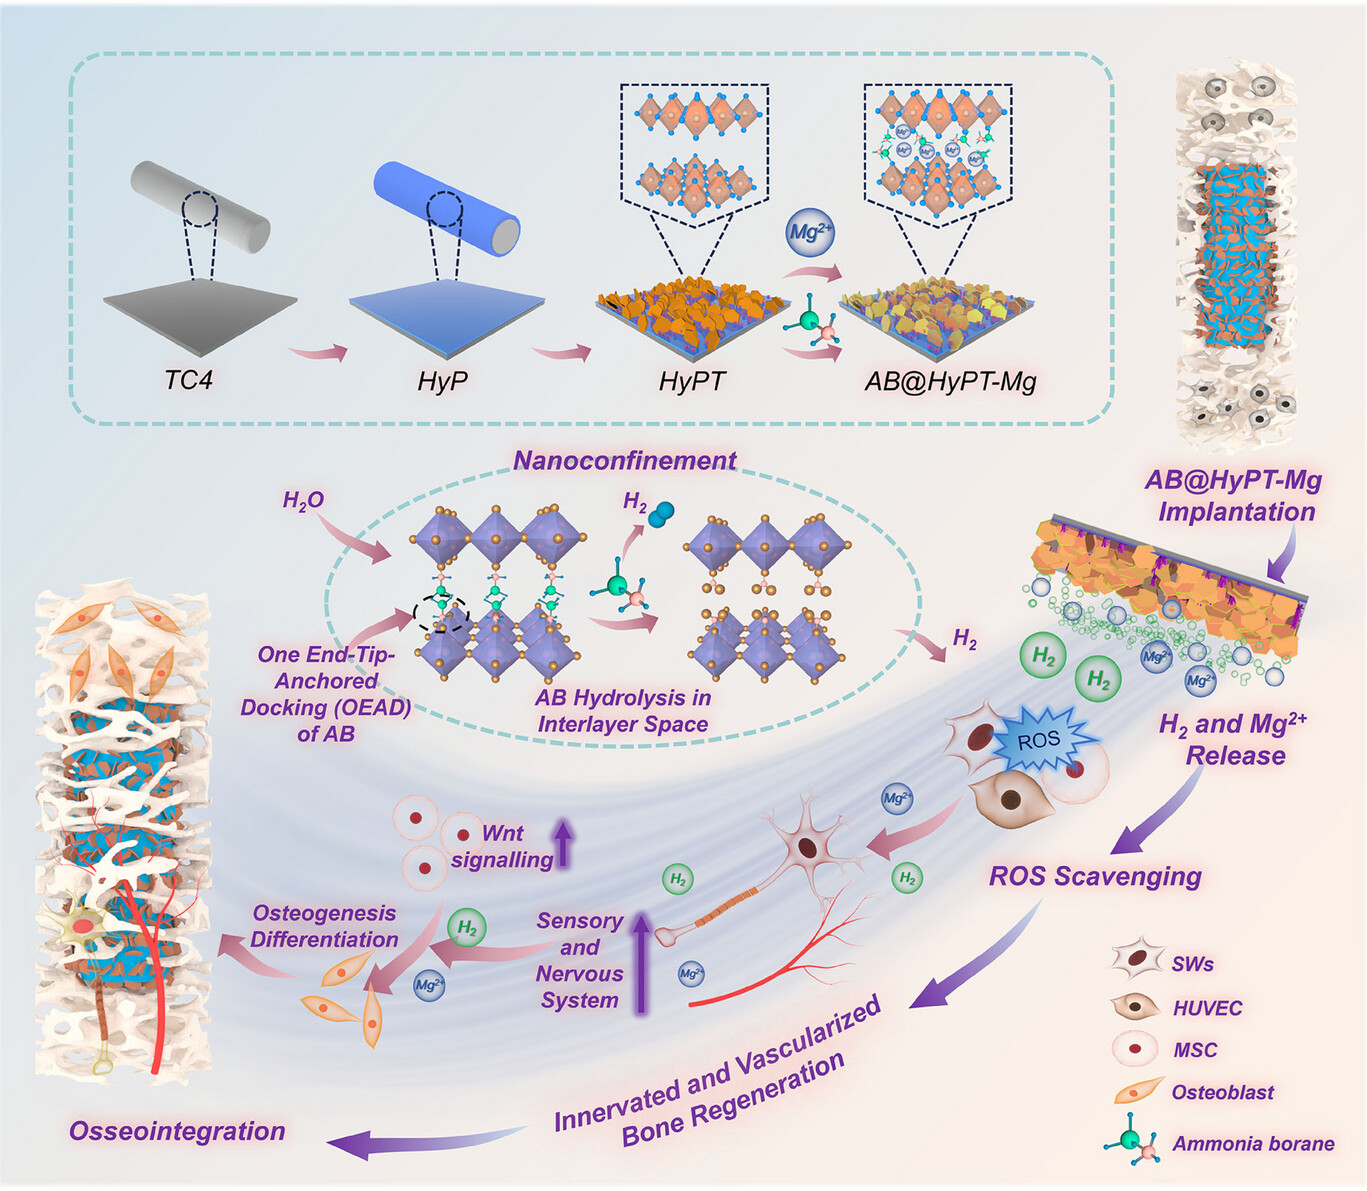

Jun 17, 2025Revolutionizing Diabetic Bone Repair: Innovative Implant Delivers Sustained Hydrogen TherapyResearchers develop an innovative implant delivers allowing for controlled and sustained H2 release to facilitate bone repair in diabetic conditions. Diabetes, a chronic metabolic disease marked by high blood sugar, is linked to complications that hinder tissue repair and immunity. Diabetic patients face significantly higher orthopedic implant f...